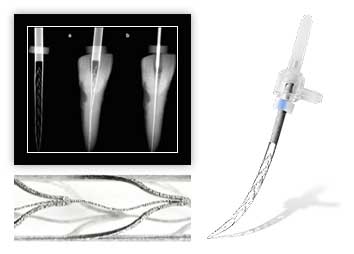

Хирургическое лечение происходит уже с препарирование корневых каналов молочного зуба, удалением участков пульпы и последующим пломбированием каналов.